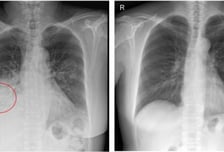

가수 클론 구준엽의 아내 쉬시위안(서희원)이 독감 후 폐렴으로 사망하면서 폐렴에 대한 궁금증과 불안감이 확산한다. 과연 폐렴은 무엇이고, 왜 생길까. 폐렴은 세균·바이러스가 폐로 침투해 염증이 생긴 병이다. 폐렴구균으로 인한 '세균성 폐렴'이 흔하다. 가톨릭대 서울성모병원 호흡기내과 민진수 교수는 "폐렴구균은 평소에도 코·목의 점막에 상주한다"면서도 "우리 몸의 면역력이 약해지면 폐렴구균이 폐·뇌·혈관·귀까지 침투해 폐렴·수막염 등을 일으킨다"고 설명했다. 독감·감기에 걸린 환자는 이차적으로 세균성 폐렴에 걸리기 쉽다. 이는 바이러스로 인해 기관지·폐점막이 손상당하면서 폐의 방어 작용이 약해지고, 그 틈을 타서 폐렴구균이 쉽게 폐에 침투하게 돼서다. 폐렴의 초기 증상은 발열·기침·가래 등 일반 감기와 비슷하다. 하지만 폐렴구균이 본격적으로 활동하기 시작하면 고열·기침·가슴 통증·호흡곤란을 유발한다. 숨이 가빠지면 호흡수도 많아져 1분당 20회를 초과하는 게 특징이다. 폐렴구균으로